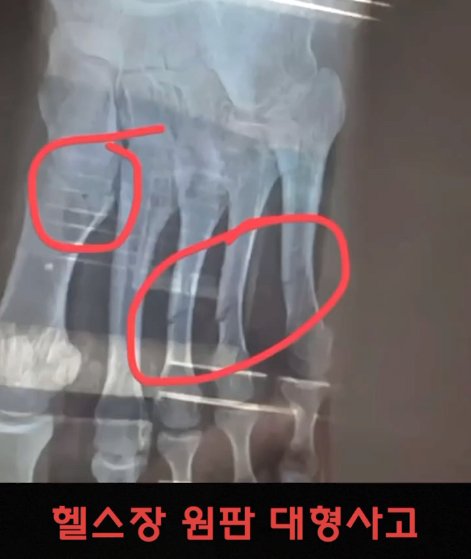

(약혐) 헬스장에서 발생하는 대형 사고

1419